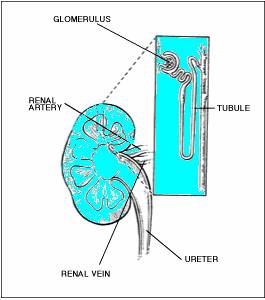

Kidneys are 2 in number, fist-sized and located on either side of the spine below the rib cage. When our bodies digest the protein we eat, the process creates waste products. In the kidneys, millions of tiny blood vessels (capillaries) with even tinier holes in them act as filters. As blood flows through the blood vessels, small molecules such as waste products squeeze through the holes. These waste products become part of the urine. Useful substances, such as protein and red blood cells, are too big to pass through the holes in the filter and stay in the blood.

Each kidney has large number (approximately one million) nephrons- each containing individualized filtering system called glomerulus. The glomerulus has multiple blood vessels and is attached to a tubule. The blood containing impurities from the body, reaches the blood vessels in the glomerulus. In these vessels the filtration process takes place and the remaining fluid passes along the tubule. In the tubule the chemicals and water are either added or extracted according to the body’s needs. The final product of this process is the urine we eliminate. Each glomerulus functions individually and the total waste is collected and sent to the urinary bladder.

The kidneys filter and return to the bloodstream more than 200 liters of fluid every 24 hours. Approximately two liters are eliminated as urine, which flows from the kidneys through the urethra to the bladder, where it is stored for up to eight hours. The urine carries with it the waste filtered by the kidneys.